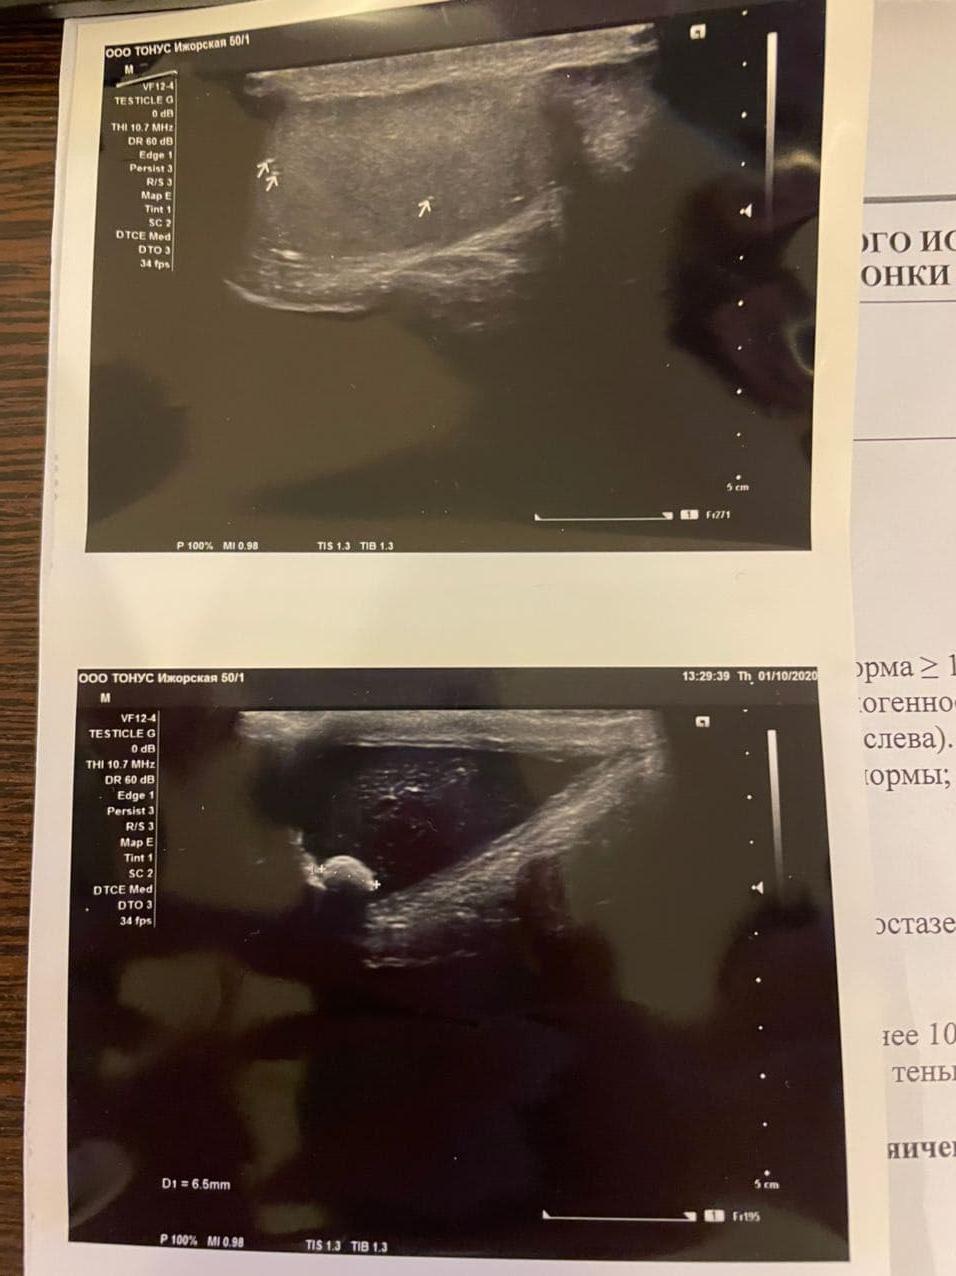

+ Зодак, якобы у меня может быть аллергия. У меня за всю жизнь не одной аллергии никогда не проявлялось)))))))))). Выйдя из кабинета я понял, что забыл рассказать про покалывания в яичках. Меня отправили на узи мошонки (Картинка). Оказалось камушек, но очень маленький.